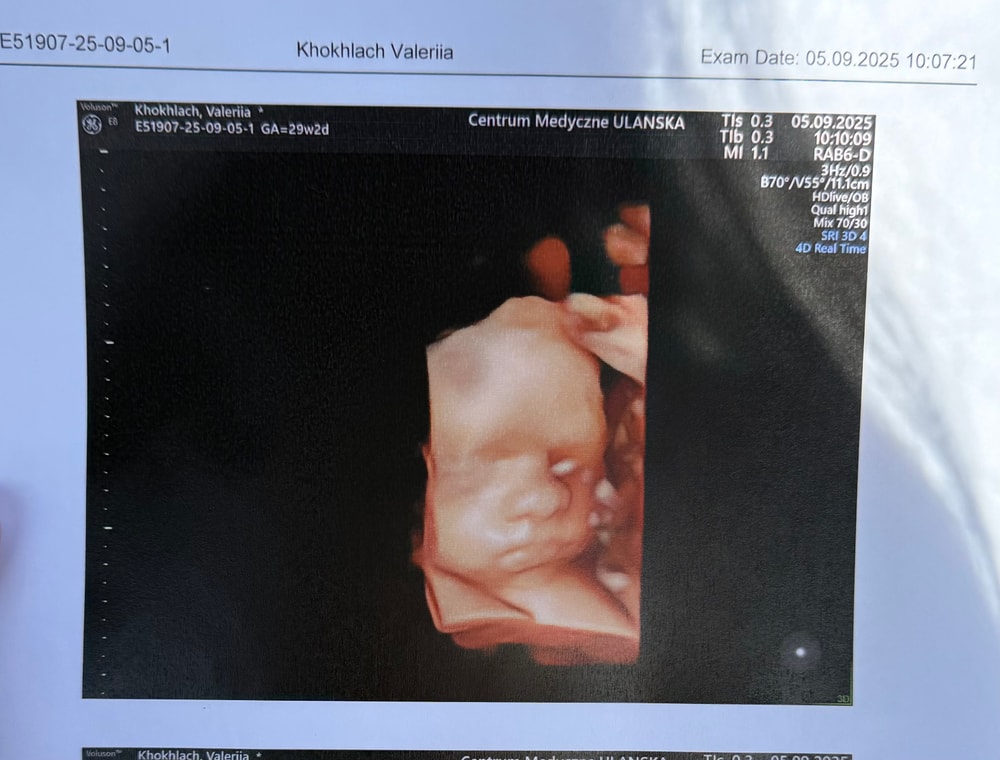

4д узи на 3 скрининге

Результаты: УЗИ, КТГ, доплера, скринингаСегодня были на 3 скрининге, у нас все отлично, уже 1250 гр.

Да, она у нас миниатюрная, даже гинеколог сказала, но добавила что она у нас всегда такой была и что это в пределах нормы, здесь в Польше делают 3 скрининг с 28 до 33 недели, сегодня у нас 29+2☺️